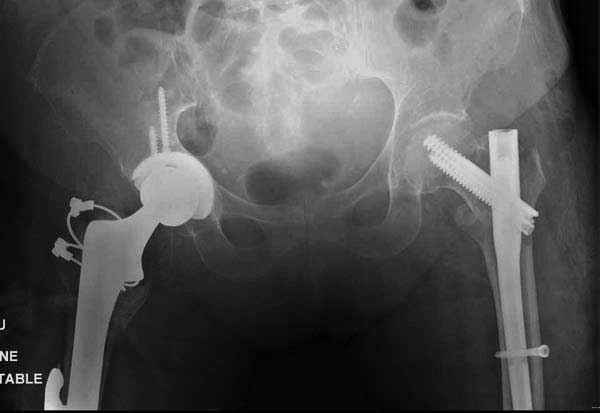

Такие “чужие осложнения” встречаются у всех и представляю банальный случай, который шаг за шагом показано как перерос в более сложный процесс... Больная 70 лет, множественные ко-морбидности, чрезвертельный перелом первоначально фиксирован Гамма 3. Осложнение в течение 6 недель, ревизия тотальной артропластикой и во время установки ножки обнаружена трещина диафиза (17), из малого доступа фиксация алло-графтом.

Обычно после чрезвертельных переломов, за исключением молодых, у пожилых остается нестабильность при движении. Часто падают и после 3х мес. в результате падения обнаружен перипротезный перелом (22-23), который зафиксирован Синтез пластиной.

Повторно поступает после двух с половиной лет, где обнаруживается перелом на второй стороне. Немного сложно, но для фиксации выбрали Antegrade InterTan Smith Nephew Nail и с момента фиксации более 3х мес.